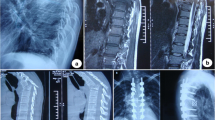

The baseline demographic details of the deformity and osteotomy of these patients are summarized in Table 1 (Fig. 1). Details of late-onset neurological deficits, including preoperative status and postoperative improvement, are summarized in Table 2 (Fig. 2).

Standing radiographs and images of a 50-year-old male patient with severe post-tubercular kyphosis. a, b Preoperative lateral and antero-posterior radiographs, demonstrating severe angular kyphosis, with preoperative kyphotic angle 86° and sagittal vertical axis 45 mm. c, d Preoperative appearance in side and posterior view. e Preoperative magnetic resonance imaging scanning demonstrates stenosis adjacent to the angular kyphosis and severe spinal compression. f Preoperative computed tomography scanning demonstrates severe angular kyphosis and “buckling collapse.” g, h Postoperative lateral and antero-posterior radiographs, showing correction of thoracolumbar kyphosis after PVCR of T11, T12, and L1, with postoperative kyphotic angle 27° and sagittal vertical axis 33 mm. i, j Postoperative lateral and antero-posterior radiographs, showing excellent correction of thoracolumbar angular kyphosis and osteotomy site fusion at the 24-month follow-up, with kyphotic angle 29° and sagittal vertical axis 42 mm. k, l Postoperative appearance in side and posterior view